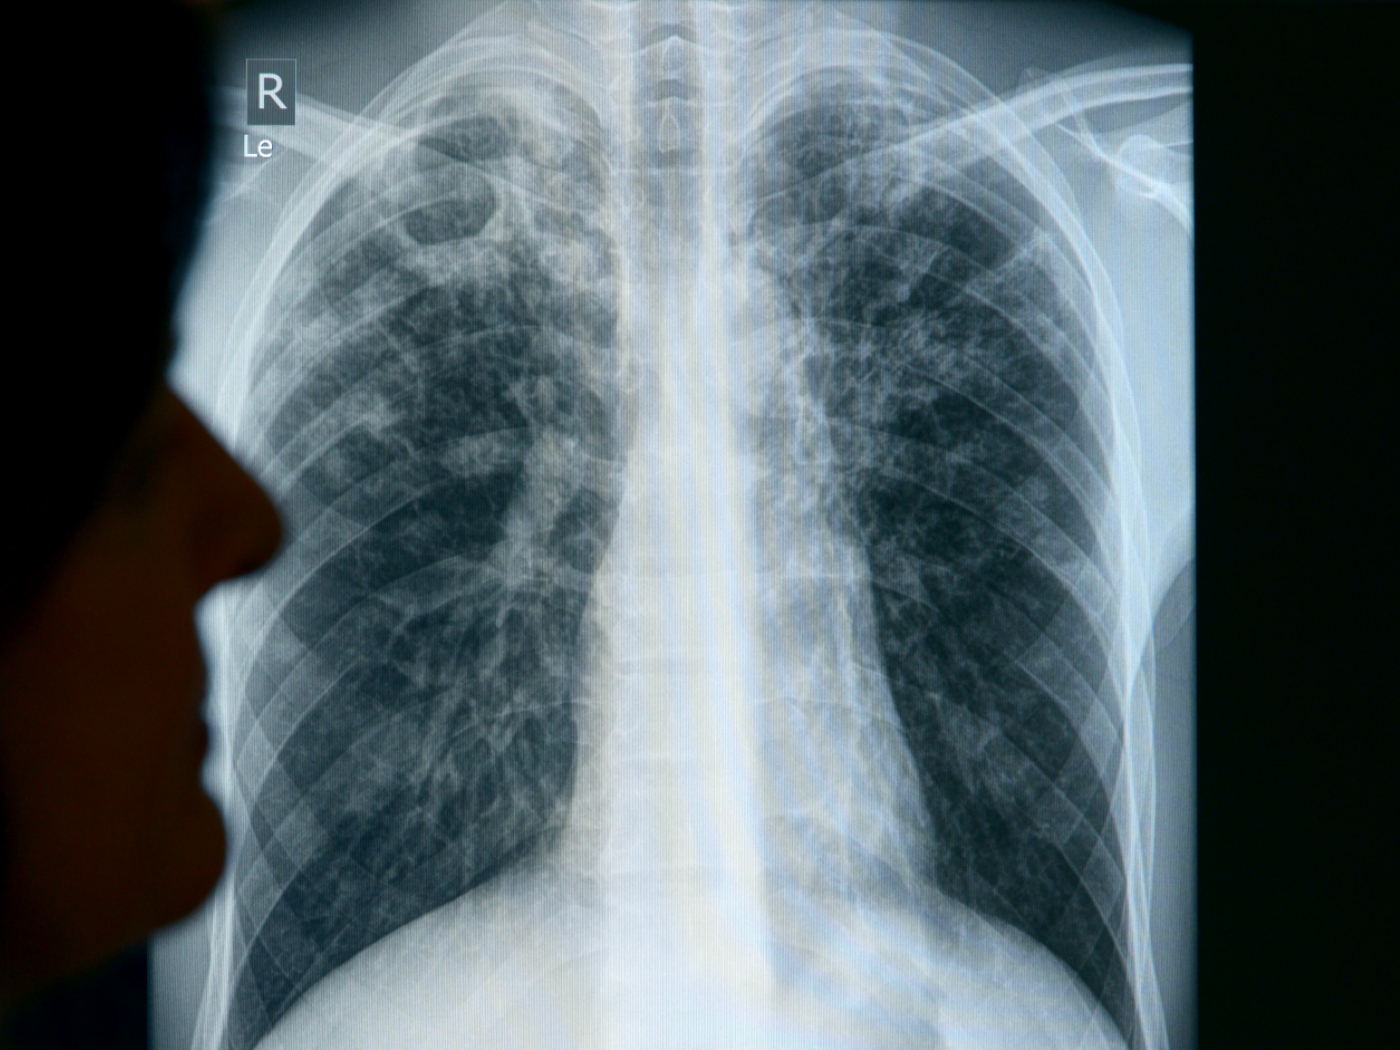

Casi di tubercolosi in aumento in Svizzera

I casi di tubercolosi sono in aumento in Svizzera, in particolare a causa dell'arrivo di persone provenienti da regioni del mondo in cui la malattia è più diffusa, ha indicato l'Ufficio federale della sanità pubblica (UFSP) a Keystone-ATS.

(Keystone-ATS) Dall’inizio dell’anno sono stati segnalati 475 casi, contro i 376 e i 375 dello stesso periodo dei due anni passati, ciò che rappresenta un aumento del 26% per l’anno in corso. Va detto che l’incremento non riguarda le persone nate in Svizzera.

L’UFSP aveva già rilevato un aumento dei casi di tubercolosi nel 2023. Ad essere particolarmente colpiti sono i giovani immigrati. Tra la popolazione nata nella Confederazione, sono soprattutto gli anziani ad essere malati, ha osservato l’UFSP. Molti di loro hanno contratto la tubercolosi da giovani, quando era molto più diffusa in Svizzera.

La tubercolosi è causata da un batterio, il Mycobacterium tuberculosis. Si trasmette per via aerea, quando il malato tossisce e diffonde nell’aria piccole goccioline contenenti gli agenti infettivi, che vengono poi respirati da altri individui sani. Per essere contagiati, una persona deve rimanere nella stessa stanza del malato per diverse ore.

Esiste un vaccino, ma non è disponibile in Svizzera. Secondo l’UFSP, la tubercolosi può essere curata molto bene con l’assunzione di antibiotici speciali per diversi mesi. Se non viene trattata, la malattia spesso si conclude con la morte.